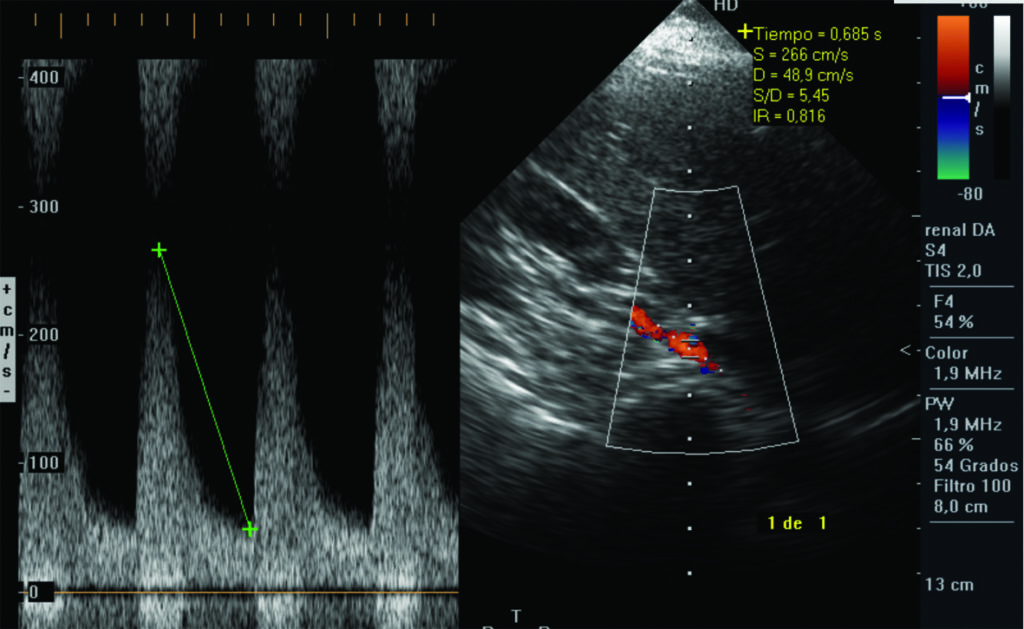

A. Velocidad del pico sistólico es la determinación de la velocidad máxima del flujo sanguíneo durante la sístole. Utilizando como criterios de estenosis los descriptos en la Tabla 1. Compartimos dos casos (Fig. 5, Fig. 6), con mediciones normales y patológicas.

| Tabla 1. Criterios de estenosis según la velocidad del pico sistólico | |

| Porcentaje de estenosis | Velocidad del pico sistólico |

| 0-59% | <220 cm/s |

| 60-79% | 220-300 cm/s |

| 80-99% | >300 cm/s |

Habitualmente se puede obtener un espectro de onda para el análisis de la velocidad del pico sistólico en el 92% de los casos. En el 8% restante, la arteria renal se visualiza parcialmente.

Consideramos que el eco Doppler color es útil para determinar el grado de evolución de la enfermedad renovascular, es decir, si la estenosis es moderada o severa, con el objetivo de instituir las medidas terapéuticas necesarias para preservar la función renal. La historia natural de estos pacientes muestra que la estenosis de la arteria renal tiende a progresar en el 20 a 40% de los casos y frecuentemente lleva a la oclusión del vaso comprometido. La presencia de flujo turbulento a nivel de la estenosis aumenta la agregación plaquetaria favoreciendo la trombosis y por ende la progresión de la lesión estenótica.